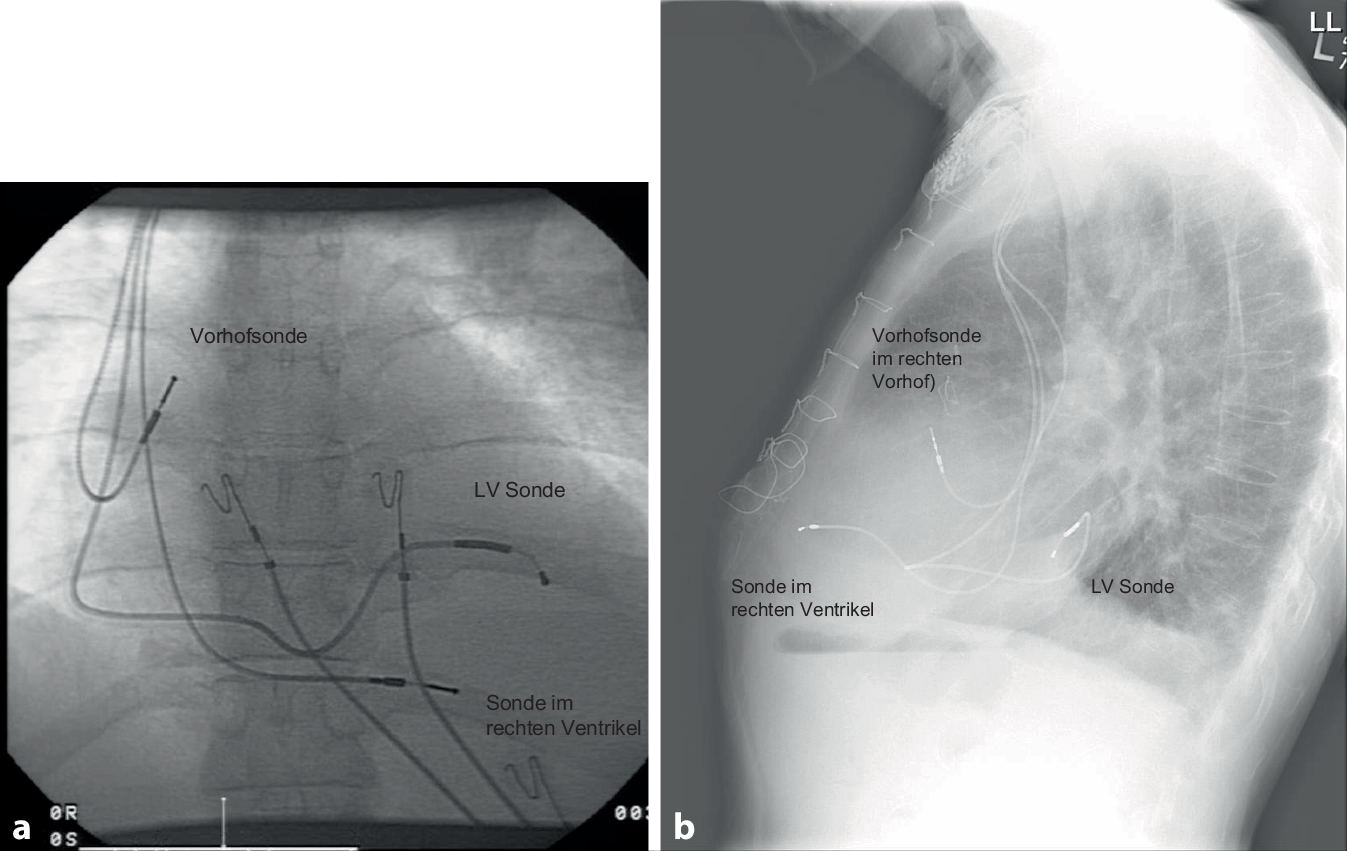

Postoperativ sollte eine PA- und laterale Röntgenaufnahme des Thorax gemacht werden, um die angemessene und stabile Position der LV-Elektrode zu bestätigen (Abb. 12). Außerdem sollte im Rahmen der ersten Nachsorge ein EKG aufgezeichnet werden, das die intrinsische Erregung, RV-Stimulation, LV-Stimulation und biventrikuläre Stimulation dokumentiert. Dies kann als Referenz z. B. für einen Stimulationsverlust der LV-Sonde herangezogen werden und zusätzlich Aufschluss über die Kammerkomplexbreite unter biventrikulärer Stimulation geben. Die RV/LV-Synchronität könnte hier optimiert werden, obwohl der klinische Nutzen im Vergleich zur AV-Zeit-Optimierung weiterhin fraglich ist (Abb. 13).

Abb. 12

Posterior-anteriore (a) und laterale (b) Röntgenaufnahme des Thorax, die eine gute Position der LV-Elektrode bei einer De-novo-CRT-D-Implantation zeigen